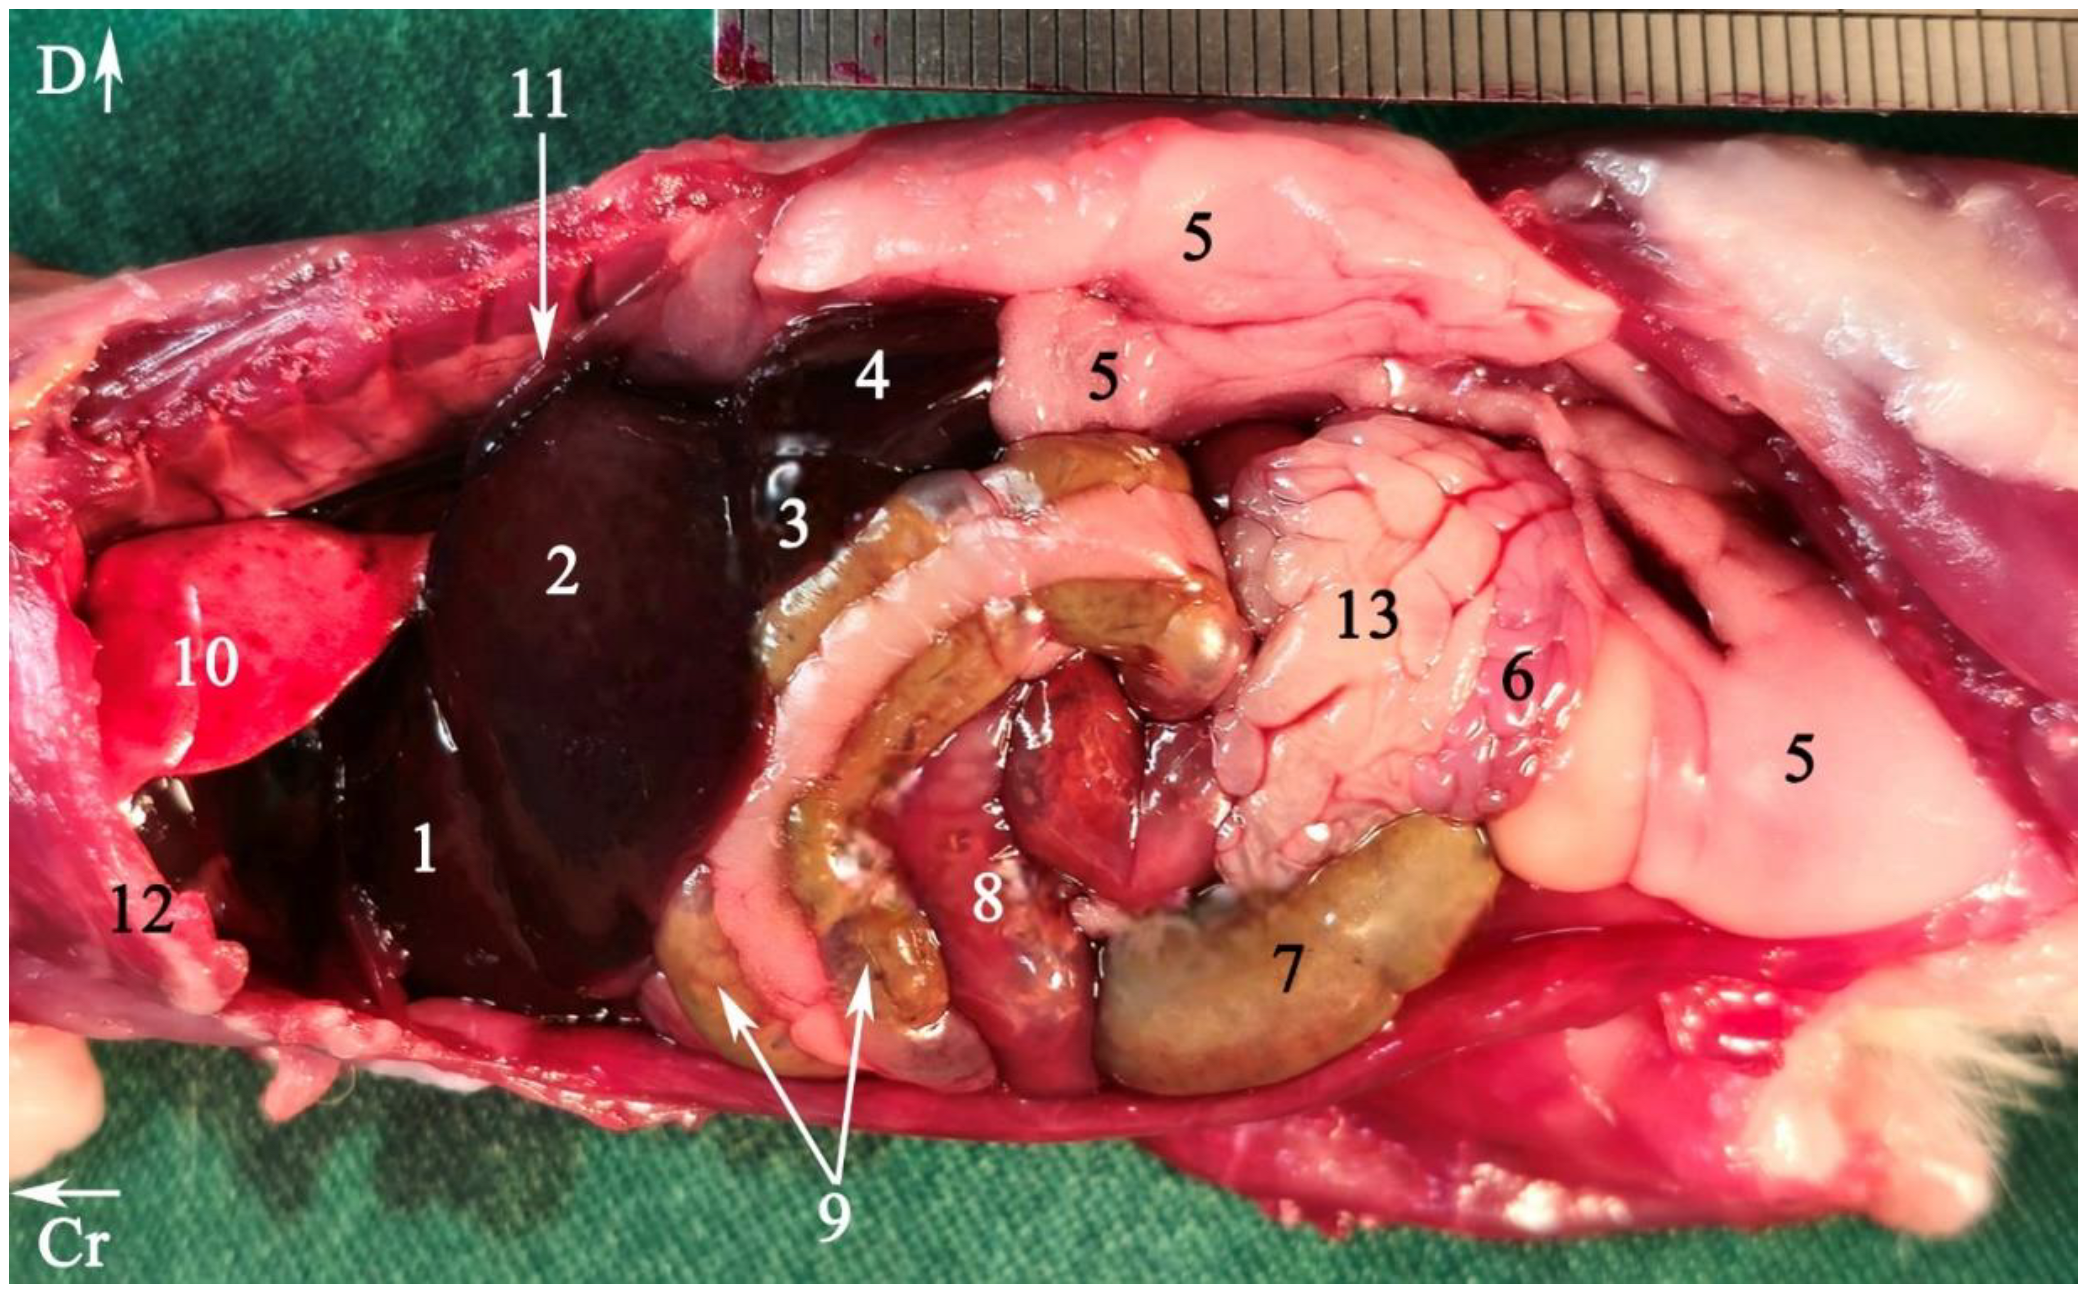

3.1. Topographic Anatomy

2.5.1. Topographic Anatomy